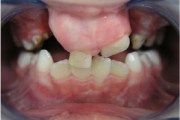

Huule-suulaelõhe ehk rahvakeeli jänesemokk on sünnidefekt, mis tekib loote arengu käigus. Tavaliselt arenevad suu ja nina välja 6. ja 12. nädala vahel. Mõnel lapsel ei kasva aga osa huulest ja suulaest kokku. Kuna huuled ja suulagi arenevad erinevalt, võib lapsel olla lõhenenud huul, Loe edasi »